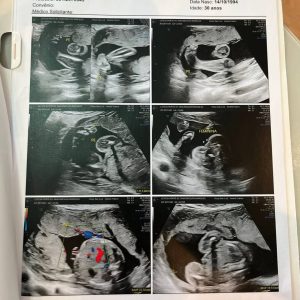

A alegria do livramento trouxe alívio, mas, semanas depois, após o segundo exame morfológico, algo corriqueiro na gravidez, outro desafio surgiu: Aurora tinha uma má-formação. “Pra gente foi uma surpresa muito grande, porque já tínhamos feito o primeiro exame morfológico, com 12 semanas, e estava tudo bem”. Para o casal era difícil entender como tudo estava bem e agora, com mais de 20 semanas, receber esse diagnóstico.

“Quando o médico pediu para conversar conosco novamente, na hora, já me bateu aquele gelo”, disse ela a respeito de como se sentiu após o exame. “Aos meus olhos, dava pra ver que um dos pés era pra dentro. Ele ainda não conseguia dizer se era só na perna, se eram os dois pés, mas identificou isso”, afirmou a mãe.

Mesmo diante do diagnóstico, o casal decidiu permanecer firme na Palavra. Letícia conta que optou por não compartilhar o diagnóstico com outras pessoas durante boa parte da gestação. “Eu tinha muita expectativa de fazer um ultrassom e ouvir que os pés estavam perfeitos. Mas, a cada exame, os médicos confirmavam a má-formação”, contou Letícia.

Até um dia antes do parto, os exames continuavam mostrando os dois pés tortos. Mesmo assim, o casal permaneceu crendo. No dia do nascimento, Letícia lembrou da primeira pergunta que fez ao marido. “Quando ela nasceu, eu perguntei: ‘Como ela está?’. Ele sabia que eu falava das pernas”, contou.

O diagnóstico anterior indicava “rotação medial bilateral dos pés” e sugeria “pé torto bilateral”. Outro médico também havia confirmado a suspeita. Porém, após o nascimento, um ortopedista avaliou a bebê e trouxe uma resposta surpreendente. “A primeira pergunta dele foi: ‘O que falaram para vocês sobre Aurora?’. Quando contamos o diagnóstico, ele respondeu: ‘Não sei por que disseram isso. Ela não tem nada. Ela é perfeita’”, contou Letícia.